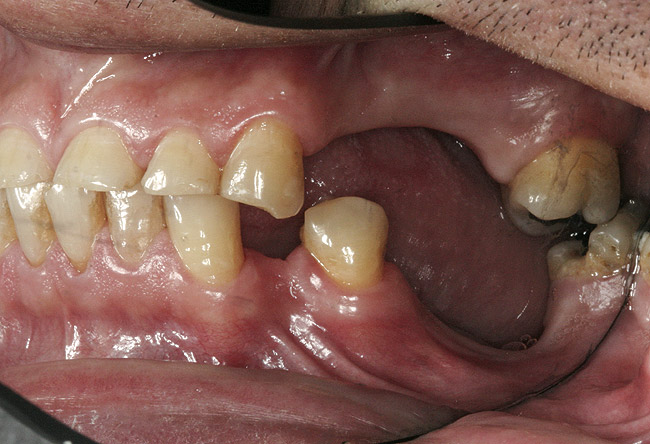

Figure 1  Intraoral anterior view of the patient presenting a severely worn maxillary dentition and loss of OVD.

Figure 1

Initial examination revealed a partial edentulous patient with extensive wear of the maxillary anterior teeth and moderate wear in the mandibular teeth (Figure 1, Figure 2, Figure 3 , Figure 4, Figure 5, Figure 6 and Figure 7). The patient's maxillary and mandibular RPDs also showed excessive wear and multiple signs of fractures (Figure 2 and Figure 3). The patient had been wearing a mandibular nightguard for 8 years.

A history of bruxing and consumption of acidic and carbonated drinks were reported. The clinical examination revealed severe tooth wear extending to the cervical level of the palatal surfaces of the maxillary teeth in some areas. Therefore, TSL was diagnosed as being caused by a combination of attrition and erosion.